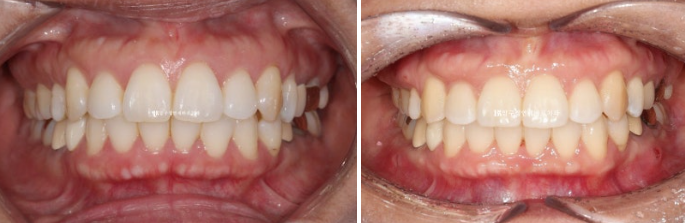

1년 7개월에 걸친 치료가 마무리가 된 후 전 후 비교입니다.

원래의 배열과 교합은 좋았어서 입안 사진에서는 뻗친 앞니 각도 개선 이외에 별로 달라진 것이 없습니다.

치료 전 후 엑스레이 중첩을 보면 재교정 효과가 잘 보입니다.

전체치열 함입과 후방이동으로 아래턱뼈의 자가회전이 꽤 많은 양 일어났습니다.

일반적으로는 2mm 정도를 목표로 치료하지만 3mm가량 일어났습니다.

무턱처럼 보이던 부분이 개선이 되고 호두턱이 풀려 아랫입술에 턱으로 이어지는 라인이 자연스럽니다.

자가회전이 되면 턱끝이 올라가고 정면에서 봤을 때 하관의 세로 길이가 짧아져서 작아보입니다.

가장 눈에 띄는 효과는 돌출 해결로 입술이 편하게 다물리는 것 입니다.

환자분들이 많이 걱정하는 팔자주름도 처음에 비하여 깊어지지 않았습니다.